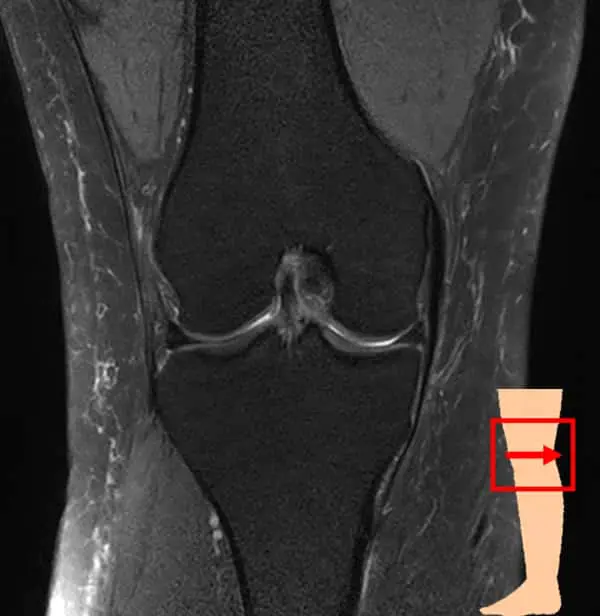

膝関節は大腿骨(太ももの骨)と脛骨(すねの骨)、腓骨(脛骨の外側にあるすねの骨)、膝蓋骨(膝のお皿)から構成されています。これらの骨を靱帯や筋肉、腱で繋いでおり、それらによって安定性を保っています。

膝関節の検査では、レントゲンの検査が一般的ですが、当クリニックではMRIを使用した検査を行なっています。

レントゲンよりも骨の内部や軟骨、半月板・靱帯の状態を把握できます。また、炎症や水が溜まっているかなどの確認も可能です。レントゲンとは違い、放射線被ばくもなく検査ができますので、体への負担が気になる方にもおすすめです。